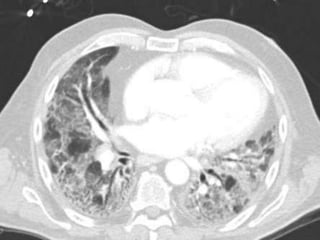

HRCT - Nodular Pattern

BRONCHIOLAR

 Centrilobular nodules: small airways of secondary lobule

 1-3mm away from pleura

 Not sub pleural

 Not on fissures or septae

Primary bronchiolar disease Mixed bronchiolar

Sharp branching nodules Peribronchiolar

Tree-in-bud ground glass nodules+/-tree-in-bud

MAI, MTB sub acute HP

Aspergillus respiratory bronchiolitis - ILD

DPB, DAB LIP

Follicular bronchiolitis Early LCH

Immune bronchiolitis – UC metastatic Calcification (CRF)

mineral dust bronchiolitis

nylon flock workers disease

Secondary to bronchiectasis

silicosis

Vascular

• Tree-in-bud/ ground glass

tumor embolism

Plexogenic arteriopathy of PAH

Tree-in-Bud Appearance

Bronchiolitis

Rare- tumor cell emboli – intralobular artery